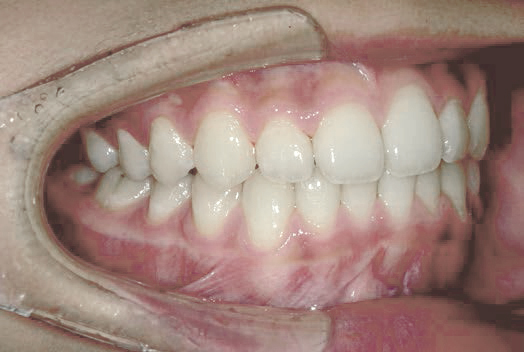

でこぼこ

部活を続けながら治療できますか? 見た目も機能も優しい矯正治療

Hさん (矯正開始時:12歳)

Before

After

上くちびるの動きの異常が確認できました。

治療を終えて

治療によってあごの成長が整い、永久歯への生えかわりも順調に進んで歯並びも綺麗になりました。

部活だけでなく、お口のトレーニングにも熱心に取り組んでくれたおかげで、上くちびるの動きも改善されました。

主訴・治療内容 バレーボールに打ち込む女の子が、歯並びは治したいけどワイヤーは怪我が心配でつけたくない。安心して部活もできる治療をしたいと相談に来られました。

治療期間 2年半

費用 462,000円(税込)